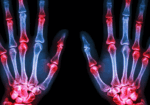

Handtherapeuten begegnen häufig Patienten mit Fingerschmerzen, Knacken und Schwierigkeiten beim Sehnengleiten. Zu den am häufigsten verwechselten Erkrankungen gehören auslösen Finger, Subluxation Sagittalbandverletzung und Subluxation Laterales Band. Jede dieser Pathologien beinhaltet unterschiedliche anatomische Strukturen und biomechanische Störungen, doch ihre überlappenden klinischen Merkmale können eine genaue Diagnose erschweren. Das Verständnis der subtilen Unterschiede im Erscheinungsbild und die Durchführung gezielter körperlicher Untersuchungen sind für eine angemessene Behandlungsplanung entscheidend.

Abzugsfinger Bei der stenosierenden Sehnenscheidenentzündung (Tendovaginitis stenosans) handelt es sich um eine Erkrankung, bei der die Beugesehne am A1-Ringband eingeklemmt wird, typischerweise aufgrund einer Verdickung oder Entzündung des Sehnen- oder Ringbandsystems. Patienten berichten häufig von einem schmerzhaften Gefühl des Einklemmens oder Blockierens im Bereich des Metakarpophalangealgelenks (MCP-Gelenk), am häufigsten im Mittel- oder Ringfinger. Bei der Untersuchung verläuft die passive Beugung typischerweise reibungslos, während die aktive Streckung auf Widerstand stoßen kann, gefolgt von einer plötzlichen Entspannung. Daher der Begriff „auslösen”-Effekt (Makkouk et al., 2008). Bei der Palpation zeigt sich häufig ein druckempfindlicher Knoten in der volaren MCP-Falte.

Subluxierendes Sagittalband Verletzung, häufig als „Boxerknöchel“ bezeichnet, tritt auf, wenn das Sagittalband die Strecksehne über dem MCP-Gelenk nicht stabilisiert. Diese Erkrankung tritt am häufigsten beim Langfinger auf, da dieser eine erhöhte Exkursion und erhöhte Traumaanfälligkeit aufweist. Klinisch berichten Patienten über ein Reißen oder Verschieben der Strecksehne bei Beugung und Streckung des MCP-Gelenks. Der typische Befund bei der körperlichen Untersuchung ist eine sichtbare oder tastbare ulnare Subluxation der Strecksehne bei Beugung und Streckung des MCP-Gelenks mit Widerstand (Rayan & Young, 2006). Schmerzen sind typischerweise dorsal über dem MCP-Gelenk lokalisiert, und es kann eine Schwellung vorhanden sein.

Subluxierendes Lateralband Verletzungen sind seltener und treten häufig bei Patienten mit Bindegewebserkrankungen (z. B. rheumatoider Arthritis) oder nach einem Trauma auf. Die lateralen Bänder, die zur PIP-Extension beitragen, können aufgrund von Rissen oder Laxheit der transversalen retinakulären Bänder volar oder dorsal subluxieren. Bei volarer Subluxation können die lateralen Bänder als Beuger des PIP-Gelenks und nicht als Strecker fungieren und so eine Knopflochdeformität imitieren. Bei der Untersuchung können Therapeuten eine PIP-Flexion mit DIP-Hyperextension und eine laterale Bandbewegung bei aktiver PIP-Flexion/-Extension beobachten. Palpation kann eine Bandinstabilität bei widerstandenen PIP-Bewegungen feststellen (Harris & Rutledge, 2016).

Diese Erkrankungen werden oft verwechselt, da sie alle mit Klicken, Schmerzen in der Nähe des MCP-Gelenks und Funktionsstörungen bei der Sehnenexkursion einhergehen können. Zum Beispiel: Subluxation Sagittalband kann imitieren auslösen Finger in frühen Stadien, wenn die Sehnenverschiebung ein Einklemmen verursacht. Ebenso Subluxation Laterale Bänder können mit einer sagittalen Banderkrankung verwechselt werden, wenn dorsale Schmerzen und Schnappgeräusche vorhanden, aber nicht richtig lokalisiert sind. Ohne eine gründliche Untersuchung können diese Erkrankungen falsch diagnostiziert werden, was zu suboptimalen Behandlungsergebnissen führt.

Um sie zu unterscheiden, sind Ort und Richtung der Sehnenverschiebung während der Widerstandsbewegung entscheidend. Auslösen Der Finger betrifft immer das Beugesehnensystem und ist volar tastbar, während Verletzungen des Sagittalbandes eine dorsale Instabilität am MCP verursachen und eine Subluxation des Lateralbandes die Mechanik des PIP-Gelenks beeinträchtigt. Provokationstests, wie z. B. Widerstand gegen die MCP-Extension (beim Sagittalband), aktive PIP-Flexion (beim Lateralband) oder Palpation am A1-Ringel während der Fingerbewegung (beim Schnellfinger), können helfen, die Pathologie zu isolieren.

Für eine genaue Diagnose ist auch die Berücksichtigung der Krankengeschichte des Patienten erforderlich. Verletzungen des Sagittalbandes sind häufig die Folge eines Schlag- oder Hyperextensionstraumas. auslösen Der Finger ist in der Regel atraumatisch und steht im Zusammenhang mit Überbeanspruchung oder entzündlichen Erkrankungen. Eine laterale Bandinstabilität kann mit systemischen Erkrankungen oder chronischer Gelenkbelastung zusammenhängen. Bildgebung, einschließlich dynamischer Ultraschalluntersuchungen, kann bei unklarer Diagnose weiterhelfen.

Zusammenfassend, obwohl auslösen Finger, Subluxation Sagittalbandverletzung und Subluxation Laterales Band kann ähnliche Symptome aufweisen. Das Verständnis der anatomischen Grundlagen und gezielte körperliche Untersuchungen ermöglichen eine genaue Differenzierung. Eine frühzeitige Erkennung ist entscheidend für konservative oder chirurgische Eingriffe und eine optimale funktionelle Erholung.